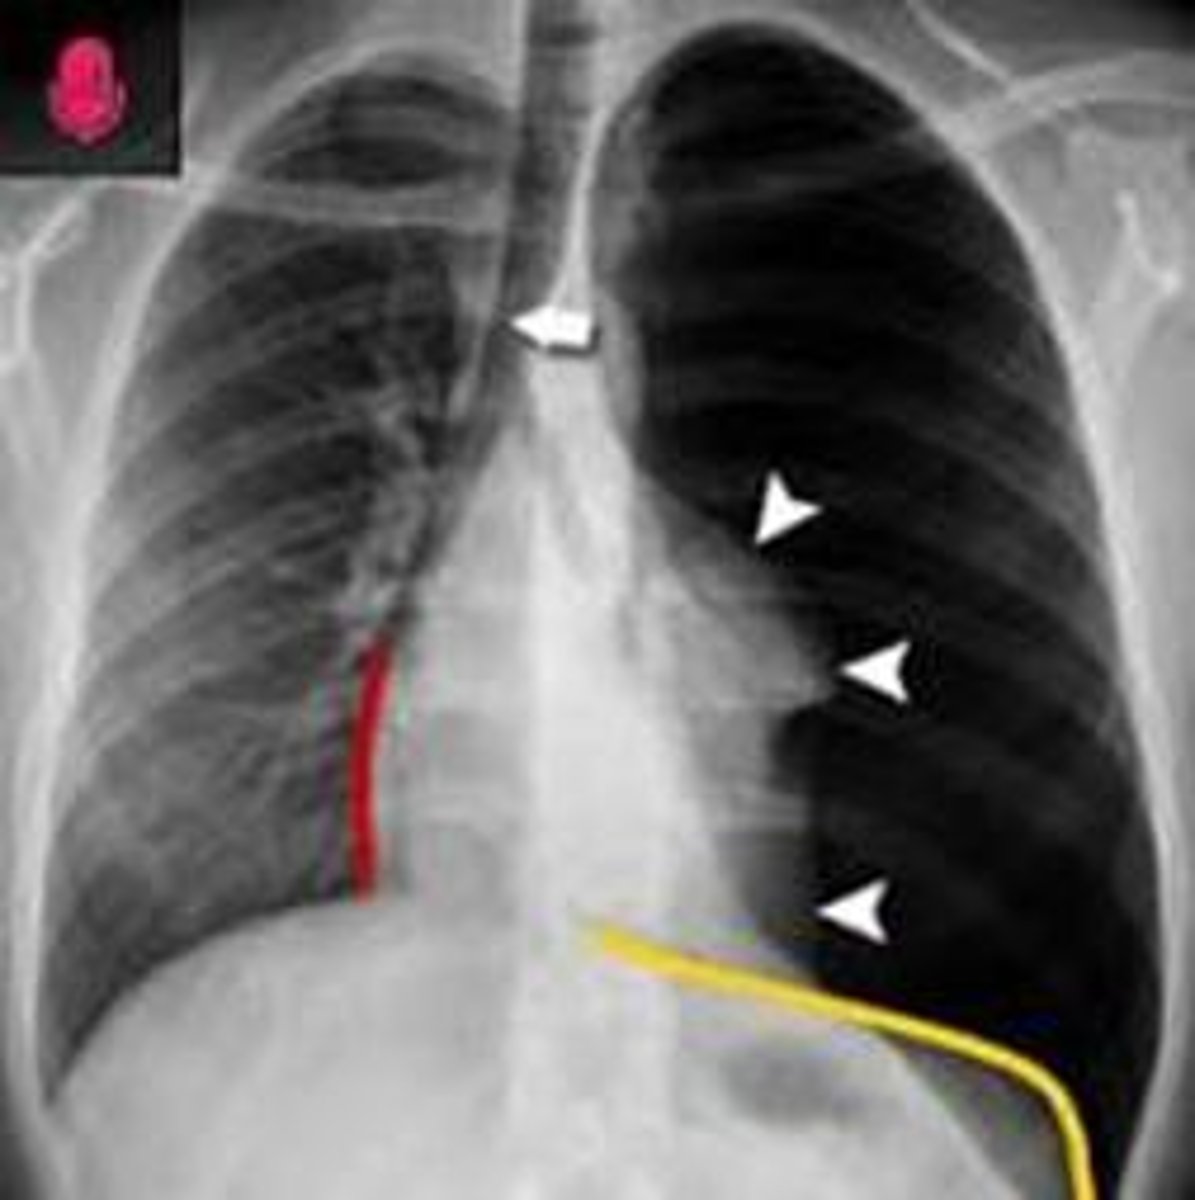

What are the hallmark clinical signs of a tension pneumothorax?

Tracheal deviation, JVD, severe hypotension, and absent breath sounds.